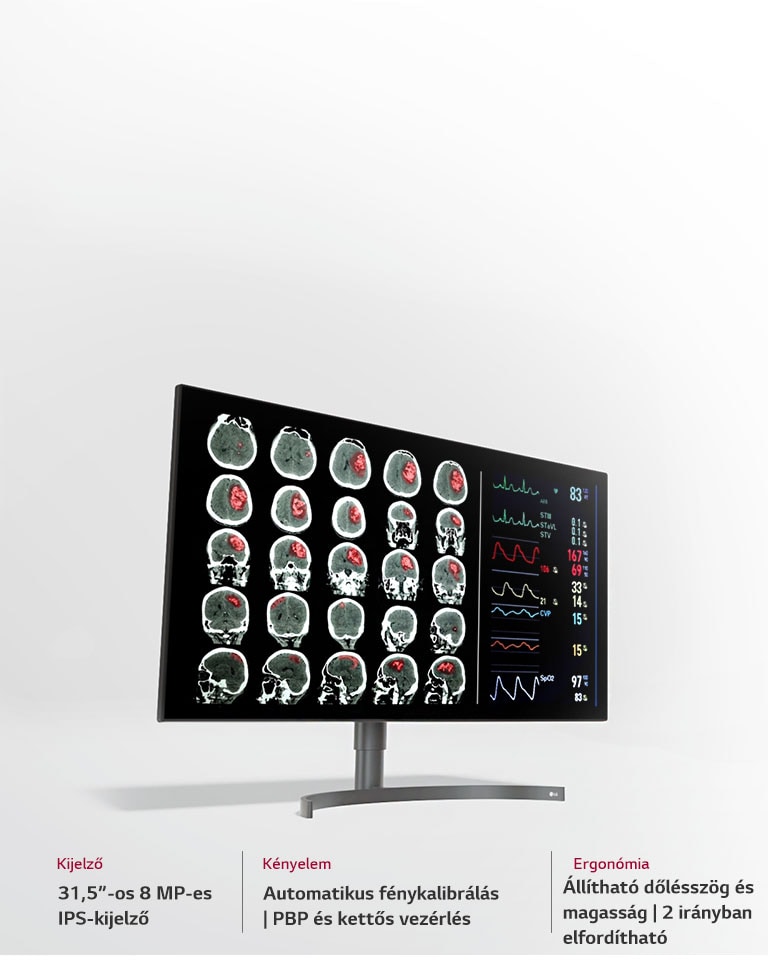

- 31,5”-os 8 MP-es IPS diagnosztikai kijelző

- Ergonomikus, professzionális kialakítás

A LG 32HL512D-B egy professzionális diagnosztikai monitor, amely kifejezetten egészségügyi és klinikai környezetbe készült. A 31,5” méretű, 8 megapixeles IPS kijelző részletgazdag, torzításmentes képet biztosít, támogatva a pontos diagnózist radiológiai, patológiai és egyéb orvosi vizsgálatok során.

Az ergonomikus kialakítás lehetővé teszi a magasságban, döntésben és elforgatásban történő testreszabást, így a monitor hosszabb vizsgálatok során is kényelmesen használható.

Ergonomikus kialakítás – a kényelem és fókusz szolgálatában

A két irányban forgatható, ergonomikus talp és a vékony keret biztosítja az optimális diagnosztikai munkaterületet. Az LG 32HL512D lehetővé teszi, hogy a monitorokat álló helyzetben helyezze el egymás mellett, így a részletek könnyen áttekinthetők, a hosszú munkafolyamatok pedig kényelmesebbé válnak.

Ergonómia: Állítható magasság, dönthető panel hosszabb munkavégzéshez